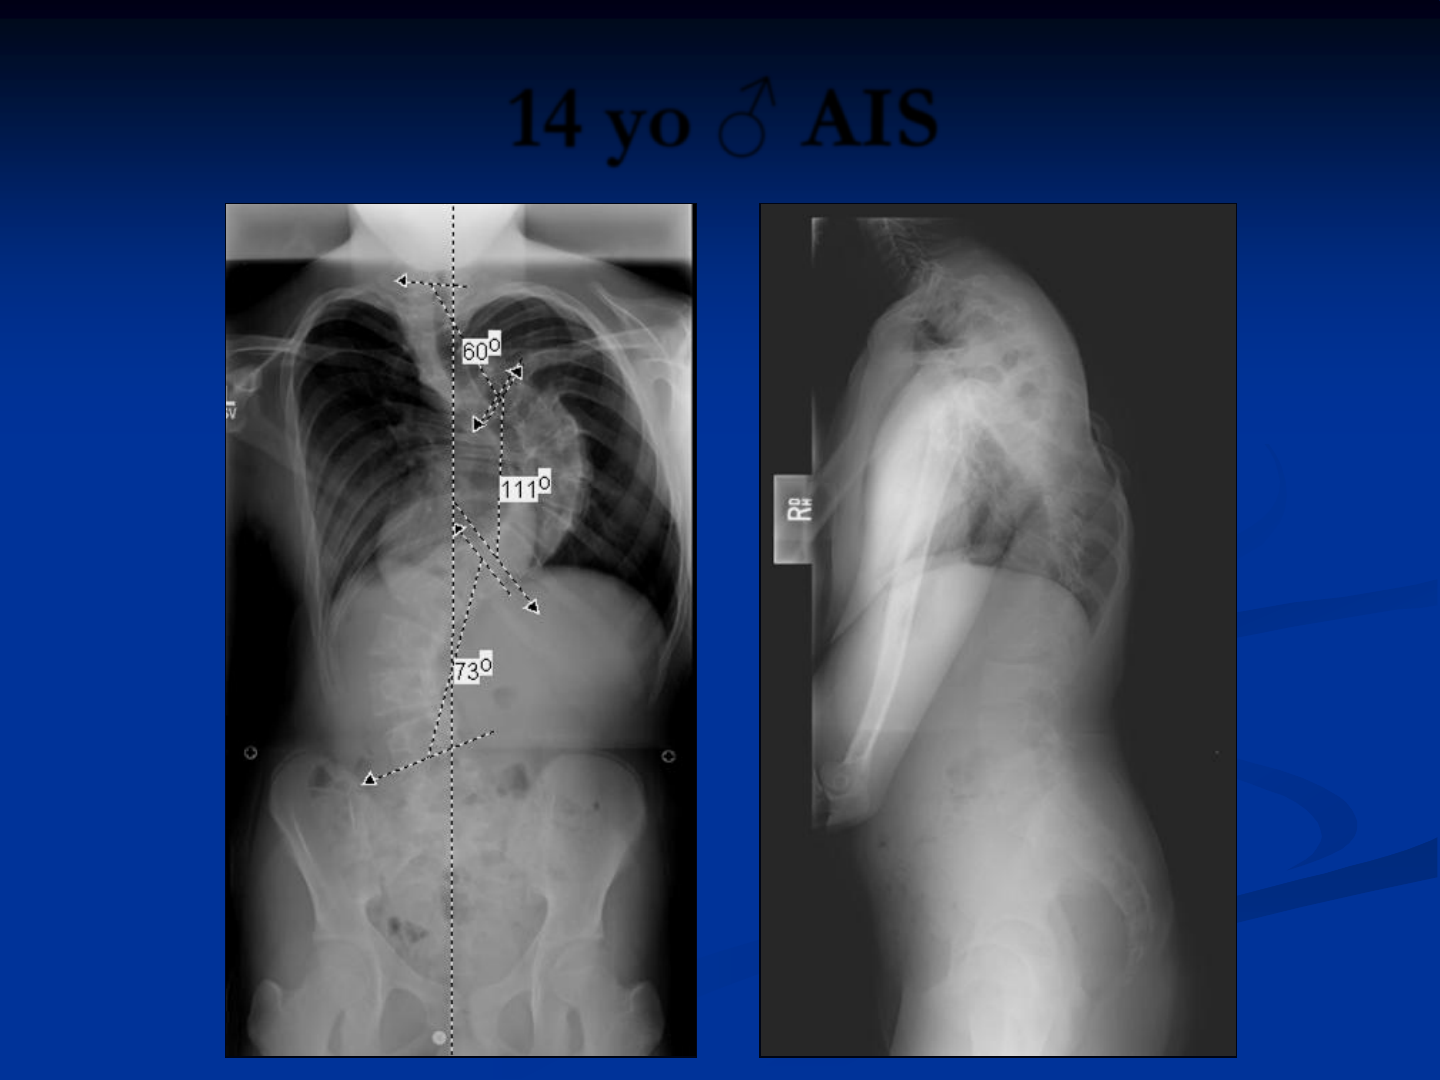

14 yo ♂ AIS

43

10/12 DA10293A, CA9232A